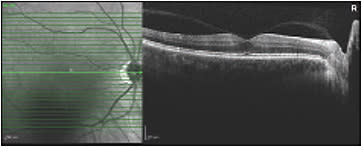

Case 3: A 64-year-old female with minimal cataract has been complaining of a prominent floater in the left eye for 2 years. This caused her difficulty with reading and driving despite her 20/20 measured acuity. She already had a posterior vitreous detachment and stated that the floater “never seems to move out of the way” (Figure 3). Video SLO confirmed this, as it is often the case that patient descriptions of their floaters exactly match video SLO findings (Video 4). She was offered surgery, which she underwent, and she was happy with the outcome. Follow-up SLO imaging shows absence of any shadowing (Figure 4).